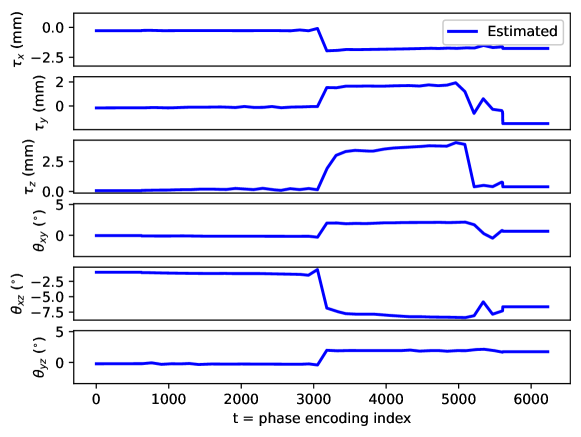

Appendix C Motion parameter estimation

The proposed motion correction algorithm described in Section 2 estimates the rigid motion that the object of interest undergoes during the scan, in order to undo its effect on the reconstructed 3D image. In 3D, the rigid motion is performed by: a plane rotation in the corresponding plane , a plane rotation in the plane, a plane rotation in the plane, a translation in the direction, a translation in the direction, and a translation in the direction (in this order). We adopt the following convention: the direction corresponds to the left-right direction, to the posterior-anterior direction, and to the inferior-superior direction, the plane corresponds to the axial plane, to the coronal plane, and to the sagittal plane. Left/right, anterior/posterior, and inferior/superior are meant from the patient perspective. The orientation of the rotation planes is determined by the right-hand rule.

By design, the prospectively-induced motion for all the experiments detailed in Section 3 follows a step-wise behavior (each step corresponding to a change of pose). In this appendix, we gather the estimated rigid motion parameters for the results shown in Section 4, as a function of time. As noted in the main body of the paper, time is equated to the phase-encoding plane coordinate index, ordered by the corresponding acquisition ordering. We display the estimated motion parameters in Figure 19 (see Sections 3.1, 4.1, Figure 2), Figure 20 (see Sections 3.1, 4.1, Figure 4), Figure 21 (see Sections 3.1, 4.1, Figure 6), Figure 22 (see Sections 3.2, 4.2, Figure 10), Figure 23 (see Sections 3.3, 4.3, Figure 12), and Figure 24 (see Sections 3.3, 4.3, Figure 14).